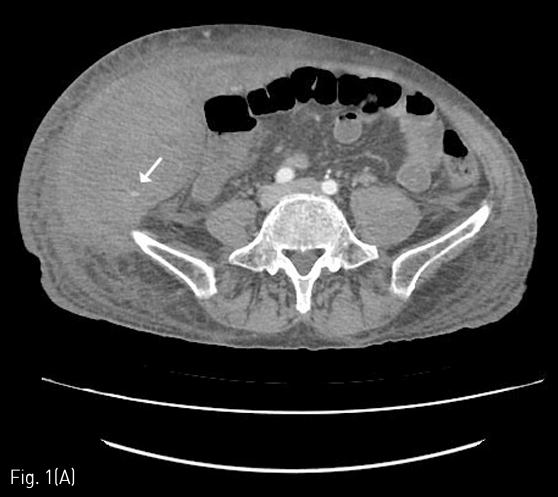

입원 중 발생한 복부와 하지의 반상출혈 및 헤모글로빈 감소로 시행한 CT에서 우측 장골회선동맥(deep circumflex iliac artery)에서의 활동성 출혈 및 우측 복벽의 혈종(13 x 9cm)이 확인되어 (Fig. 1A), Glue를 이용하여 색전술을 시행하였다(Fig. 1B). 최초 증상발생일을 기준으로 7일째 재발한 증상으로 촬영한 CT에서 혈종의 크기가 증가하였으며 (26 x 12cm), 우측 하복벽동맥(inferior epigastric artery)의 출혈병소가 관찰되어(Fig. 2A), Glue를 이용하여 2차 색전술을 시행하였다 (Fig. 2B). 다시 11일째 증상 재발하여 시행한 CT에서 혈종은 좌측 복벽에도 발생한 상태였으며 활동성 출혈병소는 우측에서만 확인되어 (Fig. 3A) 3차 응급색전술을 시행하였다. 혈관조영시 우측 장요동맥(iliolumbar artery)에서 혈관외유출이 확인되어 다시 Glue를 이용하여 색전술을 시행하였으며 (Fig. 3B), 좌측 복벽혈종의 원인 혈관은 보이지 않았다. 다시 15일째 같은 원인으로 시행한 CT에서 복벽혈종은 좌우가 연결되어 복강내 장기들을 압박하고 있었으며 크기는 약 31 x 15cm까지 커져있는 상태였고 (Fig. 4A), 좌측 서혜부에 활동성 출혈병소가 확인되어(Fig. 4B) 응급혈관조영술을 시행하였다. 혈관조영술에서 근위부 대퇴동맥과 대퇴회선 동맥(circumflex femoral artery)의 작은 분지에서 출혈병소가 확인되었으며, 각각에 대해 Gelfoam을 이용하여 색전술을 시행하였다 (Fig. 4C). 다시 같은 원인으로 26일째 CT 시행하였으며, 혈종은 더욱 커져 약 34 x 18cm까지 커지고 (Fig. 5A), 배꼽 근방에서는 피부 결손이 발생하였으며, 복강내 장기의 압박으로 양측 수신증까지 발생한 상태였다. 좌측 하복벽동맥에서 기시하는 출혈병소가 의심되었기에 다시 혈관조영술을 시행하였으며, 해당 동맥에 대해 Gelfoam을 이용하여 색전술을 시행하였다 (Fig. 5B). 추가적으로 좌측 대퇴동맥 카테터 삽입부에 가성동맥류가 형성된 것이 확인되었고 보존적으로 추적관찰하기로 하였다. 최초 색전술을 기준으로 29일째 6번째 CT를 촬영하였으며, 우측 상복벽에 새롭게 출혈병소가 확인되었다 (Fig. 6A). 다시 혈관조영술을 시행하였으며, 우측 내흉동맥에서 기시하는 근횡격막동맥 (musculophrenic artery)의 분지에서 출혈병소가 확인되어 Glue를 이용하여 색전술을 시행하였다 (Fig. 6B).

Fig 1A

(A) Abdomen CT shows hematoma of right abdominal wall (about 13 x 9cm) and an active bleeding focus from the small branch of the right deep iliac circumflex artery (arrow).